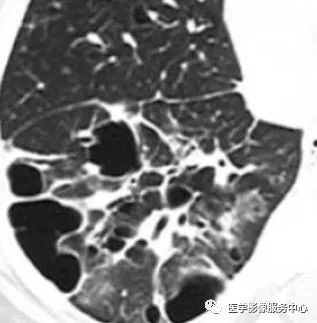

图14

图14为LIP,表现为下肺较大的含气囊腔,血管与囊壁相关(红箭头),且可见到邻近的正常支气管(绿箭头)。